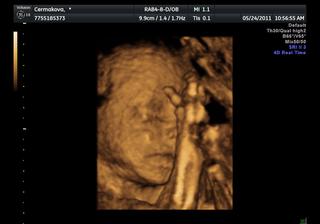

Na 3D měla pořád packy před obličejem, fotky nejsou až tak zdařilé, videa jsou některá pěkná, ale sem nejdou bohužel vložit..

@suzamen i na té fotce je krásně vidět, moc držím palečky, aby vše bylo jak má a v zimě ses dočkala zdravého miminka